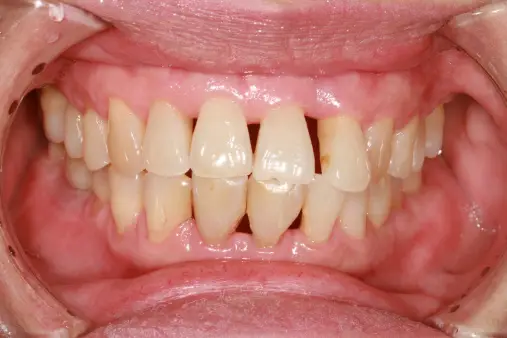

치아가 서로 맞물리는 방식에 변화가 생긴 경우, 잇몸 질환으로 인해 지지 구조가 약해져 치아가 이동할 수 있습니다. 이는 약해진 바닥에서 가구를 옮기는 것과 유사합니다. 고름은 감염의 명백한 지표이며, 피부 상처 주변의 고름이 의미하는 것과 같습니다. 또한 통증과 부종이 동반되어 식사와 양치가 고통스럽게 될 수도 있습니다. 뿌리가 노출된 경우, 뜨거운, 차가운, 달콤한 음식과 음료에 대한 민감성이 증가할 수 있습니다. 차가운 음료를 섭취할 때 치아에 날카로운 통증을 느낄 수 있습니다. 이와 같은 증상은 악성 치주염의 초기 단계로 해석될 수 있습니다. 조기 발견과 치료가 중요하며, 정기적인 구강 위생이 필요합니다. 부정확한 치주 관리로 치주염이 심화될 경우 치아를 잃는 위험이 있습니다. 치과 전문의를 방문하여 전문적인 치주 치료를 받는 것이 좋습니다. 중요키워드: 악성 치주염

- 치아 이동 및 잇몸 질환

- 고름의 의미

- 식사 및 양치질의 고통

- 민감성 증가 및 통증

- 치주염 초기 증상과 위험성